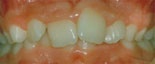

Trångställt bett

trångställt bett före behandling trångställt bett efter behandling

Före behandling av trångstätt bett Efter behandling av trångställt bett

Ett trångställt bett med för smal käke, i vy mot gommen. Således en kombination av en malocklusion och en utrymmesanomali. Om man behandlar liknande anomalier i rätt tid under ungdomsåren kan man till och med, som här, bredda käken med hjälp av tandreglering. Barnets egen växt hjälper till.